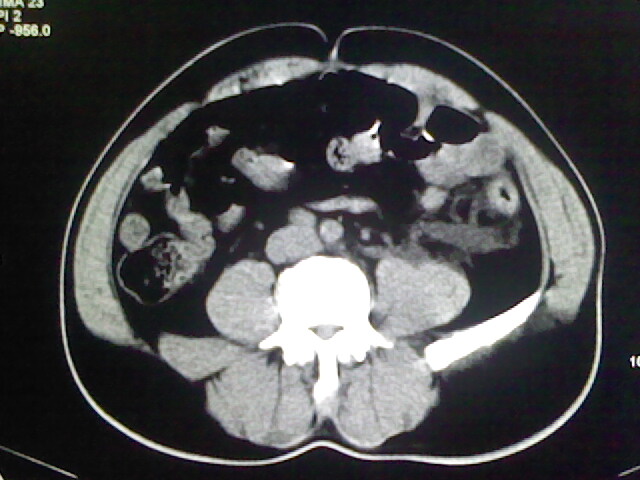

以下是引用zsl6918在2009-2-7 7:29:00的发言:[br]请提供介入的方式方法,肾及输尿管改变考虑与介入损伤有关,漏了,尿液外渗。

以下是引用余辉在2009-2-7 8:27:00的发言:[br]可能是硬化剂烧穿囊壁进入肾盂输尿管了,尿漏。不除外介入或碎石术后合并感染[br]患者术后怀疑结石,接着就碎石了?就怀疑没有确诊吗?碎石用的什么方法?气压弹道还是体外超声?如果这样的话责任人都难找

以下是引用随光逐影在2009-2-7 8:46:00的发言:[br]支持3楼意见。[br]另:不排除左肾及肾周感染可能。